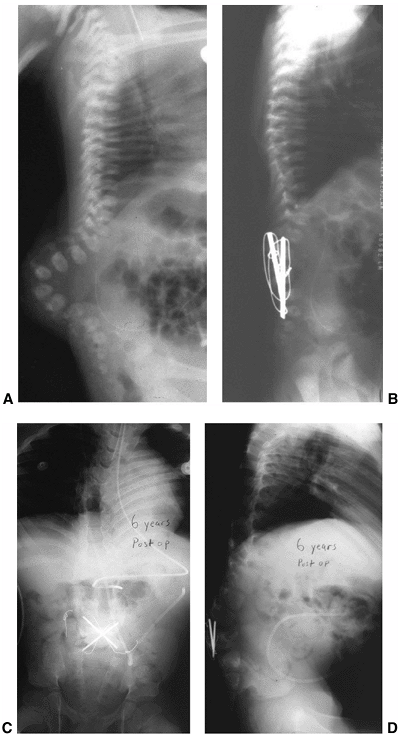

The method of surgical correction depends upon when the deformity is

diagnosed. Many neurosurgeons can decrease the rate of subsequent

kyphosis by initially resecting kyphotic vertebra at the time of sac

closure (222,235). Excision of apical vertebral bodies or tension band fixation at the time of closure will reduce the deformity (Figs. 16.10 A, B).

At the same time, dorsal reapproximation of the paravertebral muscles

will help cover the defect and, additionally, prevent further

progression of the deformity.

![]() |

|

Figure 16.10 A–D:

Newborn infant with open myelomeningocele and severe kyphosis. Closure and reduction of the kyphosis was performed simultaneously with resection of vertebral bodies and tension band fixation. B: At 6-year follow-up, the child has only mild residual kyphosis that is not progressive and does not require any further treatment. (Courtesy of Charles T. Price, MD) |

Figure 16.12 A: Anteroposterior and lateral radiographs of an 8-month-old infant with thoracic level of paralysis and C-shaped kyphosis. B:

Anteroposterior and lateral radiographs after decancellation of two vertebral bodies above and below the apex with posterior instrumentation. Rods are placed into the S1 foramen and fixed proximally with sublaminar wires in an extraperiosteal fashion. The rods are left long to allow for continued spine growth. C: Follow-up radiographs at 2 years demonstrate reduction of kyphosis and growth of the spine away from the rods proximally. Consolidation of the egg-shelled vertebrae are noted (arrows). |